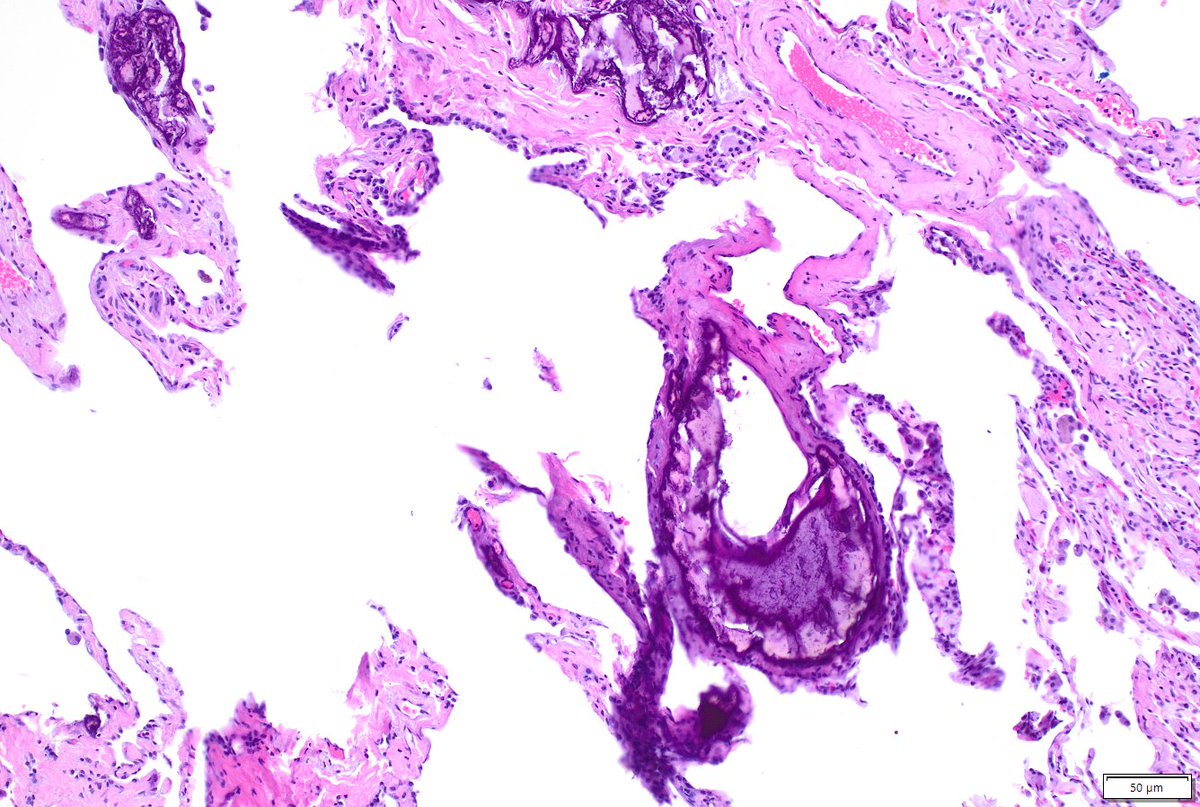

Non-neoplastic lung pathology is a major part of my work at @MoffittNews. Consider training in thoracic pathology with us! We are still accepting fellows for 2026-2027. Today’s case: metastatic pulmonary calcification in a patient after massive transfusion #lung #pathology #MedEd